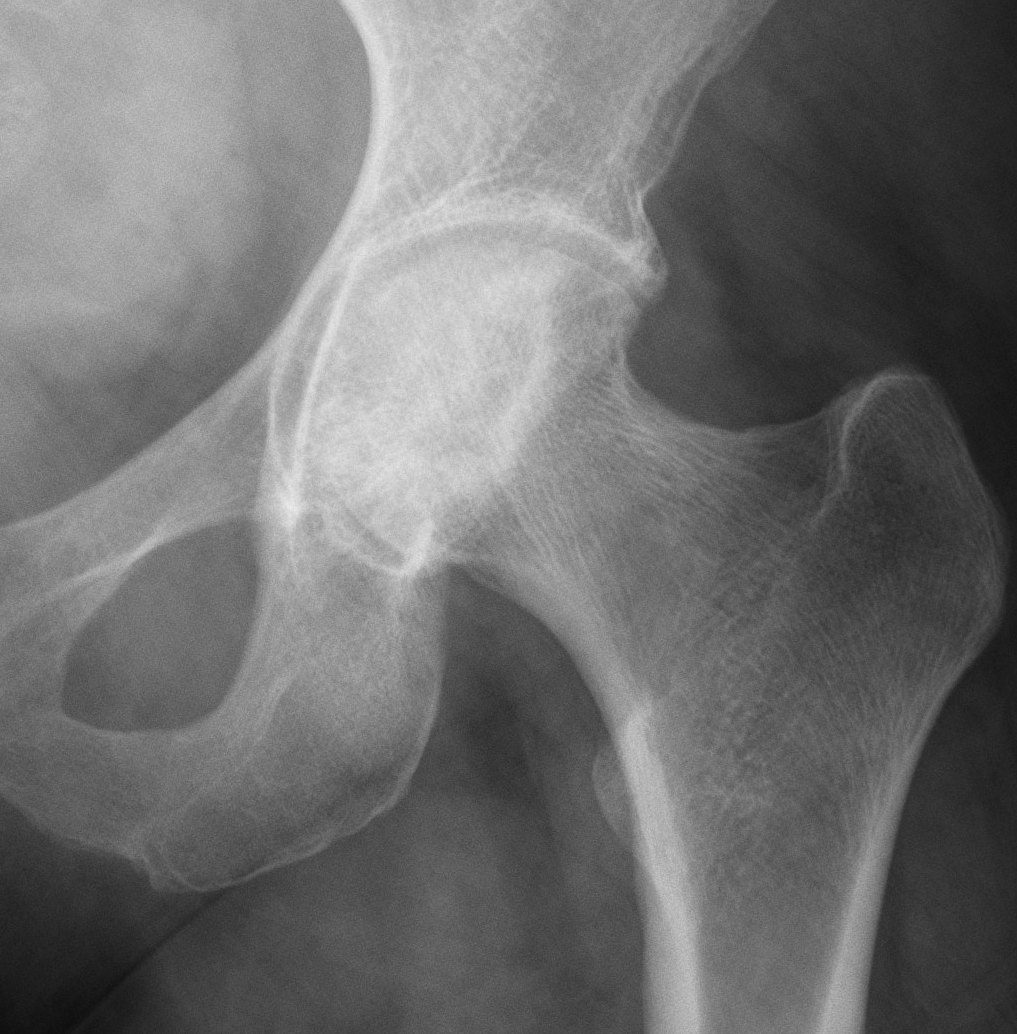

Crescent Sign

- subchondral collapse of the necrotic segment

- separation of subchondral plate from necrotic cancellous bone

Collapse

Flattening femoral head Crescent sign |

Subchondral fracture IIIA: <2mm flattening IIIB: > 2 mm flattening |

Xray

Stage II: sclerosis with cystic areas resorption, no collapse

Stage III: collapse / flattening femoral head with preserved joint space